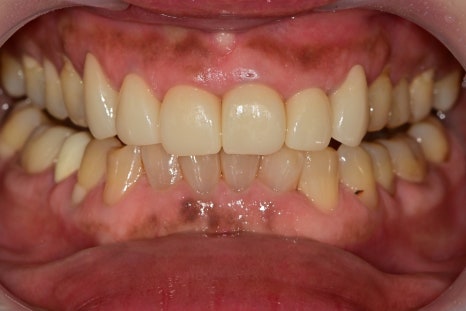

치열이 고르지 않은 위 앞니를 가지런하게 하고 싶다는 주소였습니다.

양쪽 송곳니는 오래된 보철, 수복물에 의해 재치료가 필요해 보였습니다.

나머지 4개의 앞니에서는 가운데 치아만 살짝 겹쳐 있어 보이는 것으로 보이지만

위에서 바라보는 사진은 완전히 달랐습니다.

치아가 돌출되는 정도, 좌우로 회전된 정도, 치아의 겹친 부분에서

진단 모형을 제작하기 전이였지만 치아를 고르게 하기 위해서는

치아 삭제량이 상당히 많이 필요해 보였습니다.